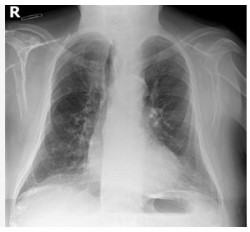

La OMS notifica más de 400.000 casos de COVID-19 en el mundo durante las 3 primeras semanas de 2024

La Organización Mundial de la Salud (OMS) ha notificado más de 400.000 nuevos casos de COVID-19 en el mundo durante las 3 primeras semanas del año, así como 7.800 muertes, más de 171.000 hospitalizaciones y 2.100 ingresos en UCI, según ha informado este jueves en durante el seminario donde han abordado qué variantes están circulando, su riesgo e impacto, y qué se puede hacer para prevenir y proteger contra infecciones.